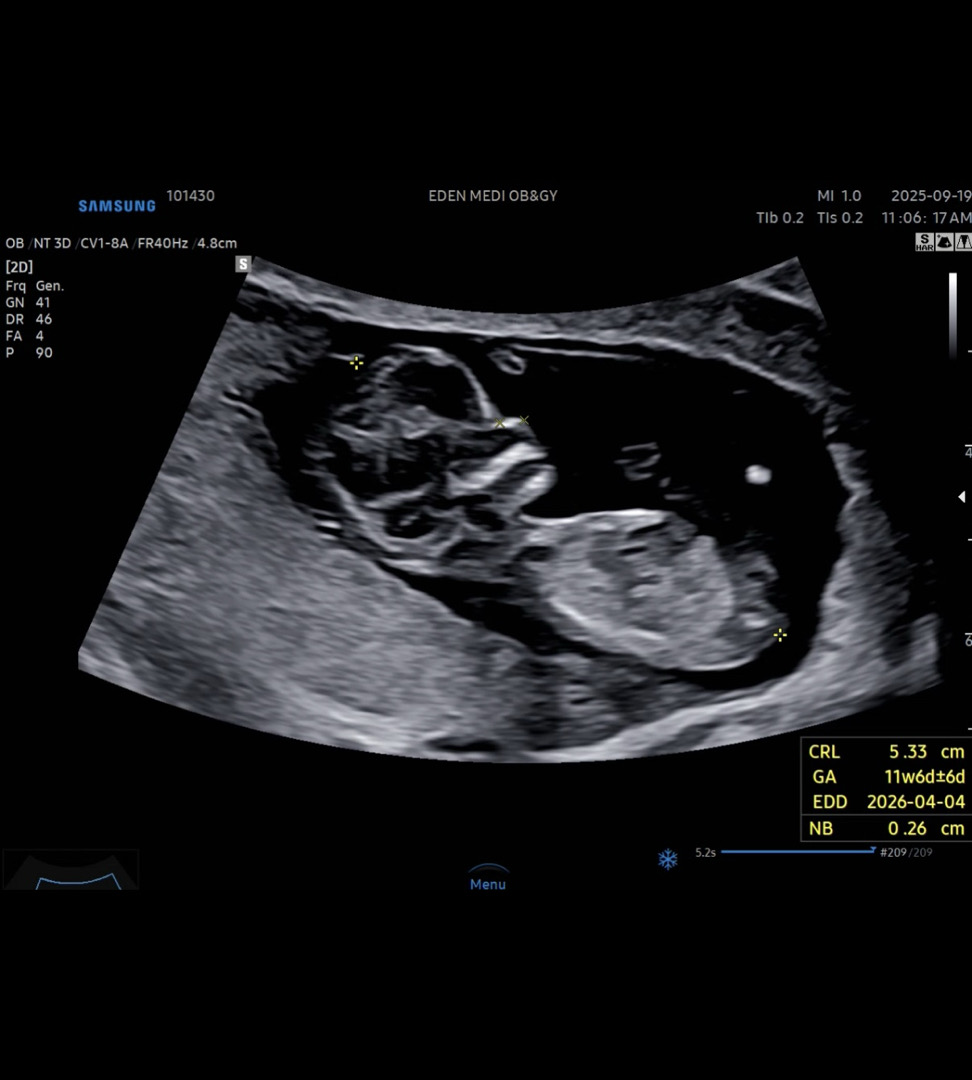

이걸로 각도법볼수있을가요?